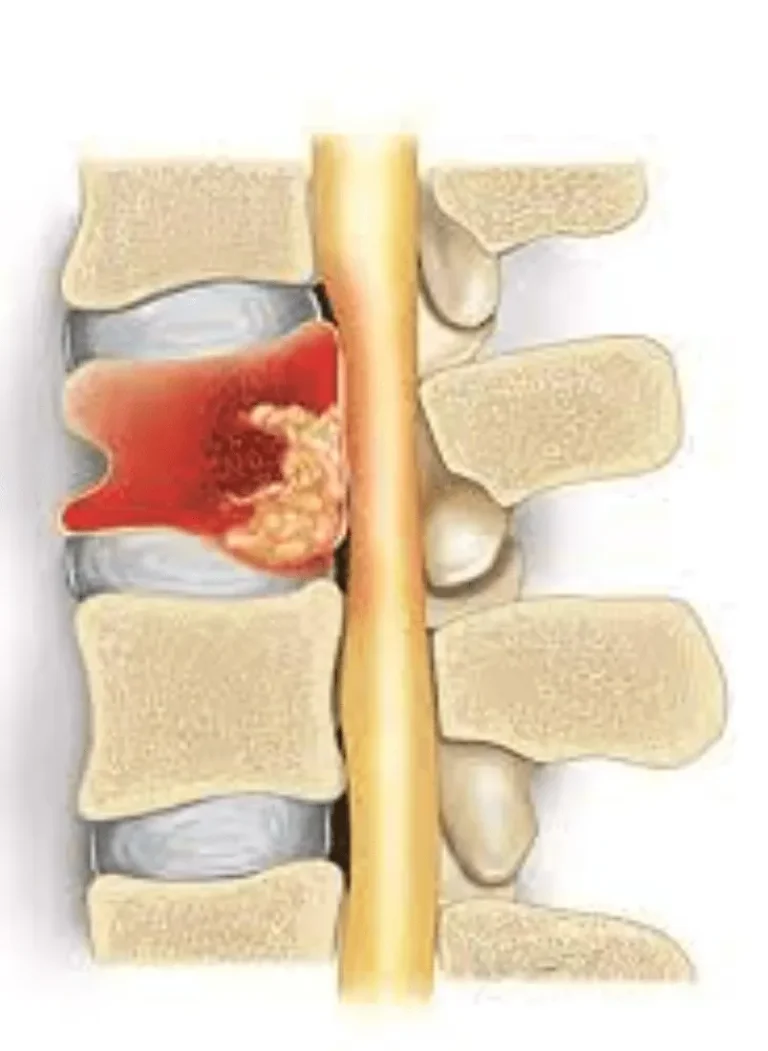

Medical scan showing normal and missing spinal bones with herniated disc, labeled for ultrasonic surgery.

Pain Source NOT Treated